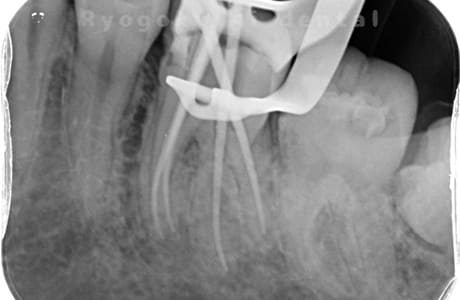

他院で細い器具(ファイル)が根管内に破折した状態で、咬合痛を主訴に来院された患者様です。ファイルをマイクロスコープ下で除去し、根管治療を行ないました。